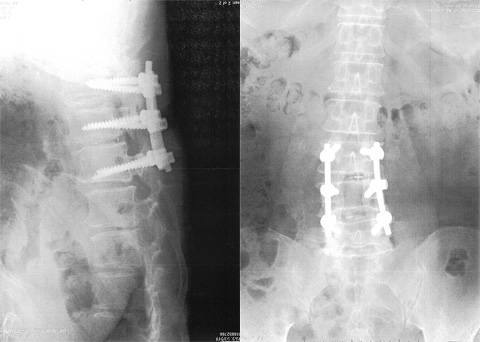

レントゲン写真を見ながら学部長(病院長に昇格している)は言った。椅子を回してこちらを向いた。

「骨融合順調。これは奥さんにプレゼントだ。」

そう言ってレントゲン写真をくれた。